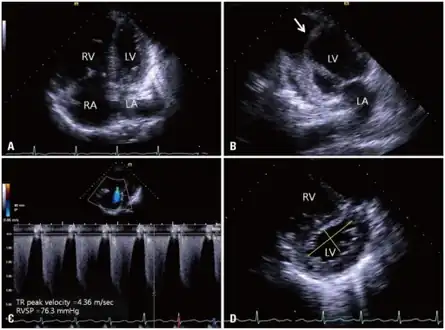

a-d)2DE (two dimensional echocardiography) features of cor pulmonale

Investigations available to determine the cause of cor pulmonale include the following:[1]

- Chest x-ray – right ventricular hypertrophy, right atrial dilatation, prominent pulmonary artery

- ECG – right ventricular hypertrophy, dysrhythmia, P pulmonale (characteristic peaked P wave)

- Thrombophilia screen- to detect chronic venous thromboembolism (proteins C and S, antithrombin III, homocysteine levels)